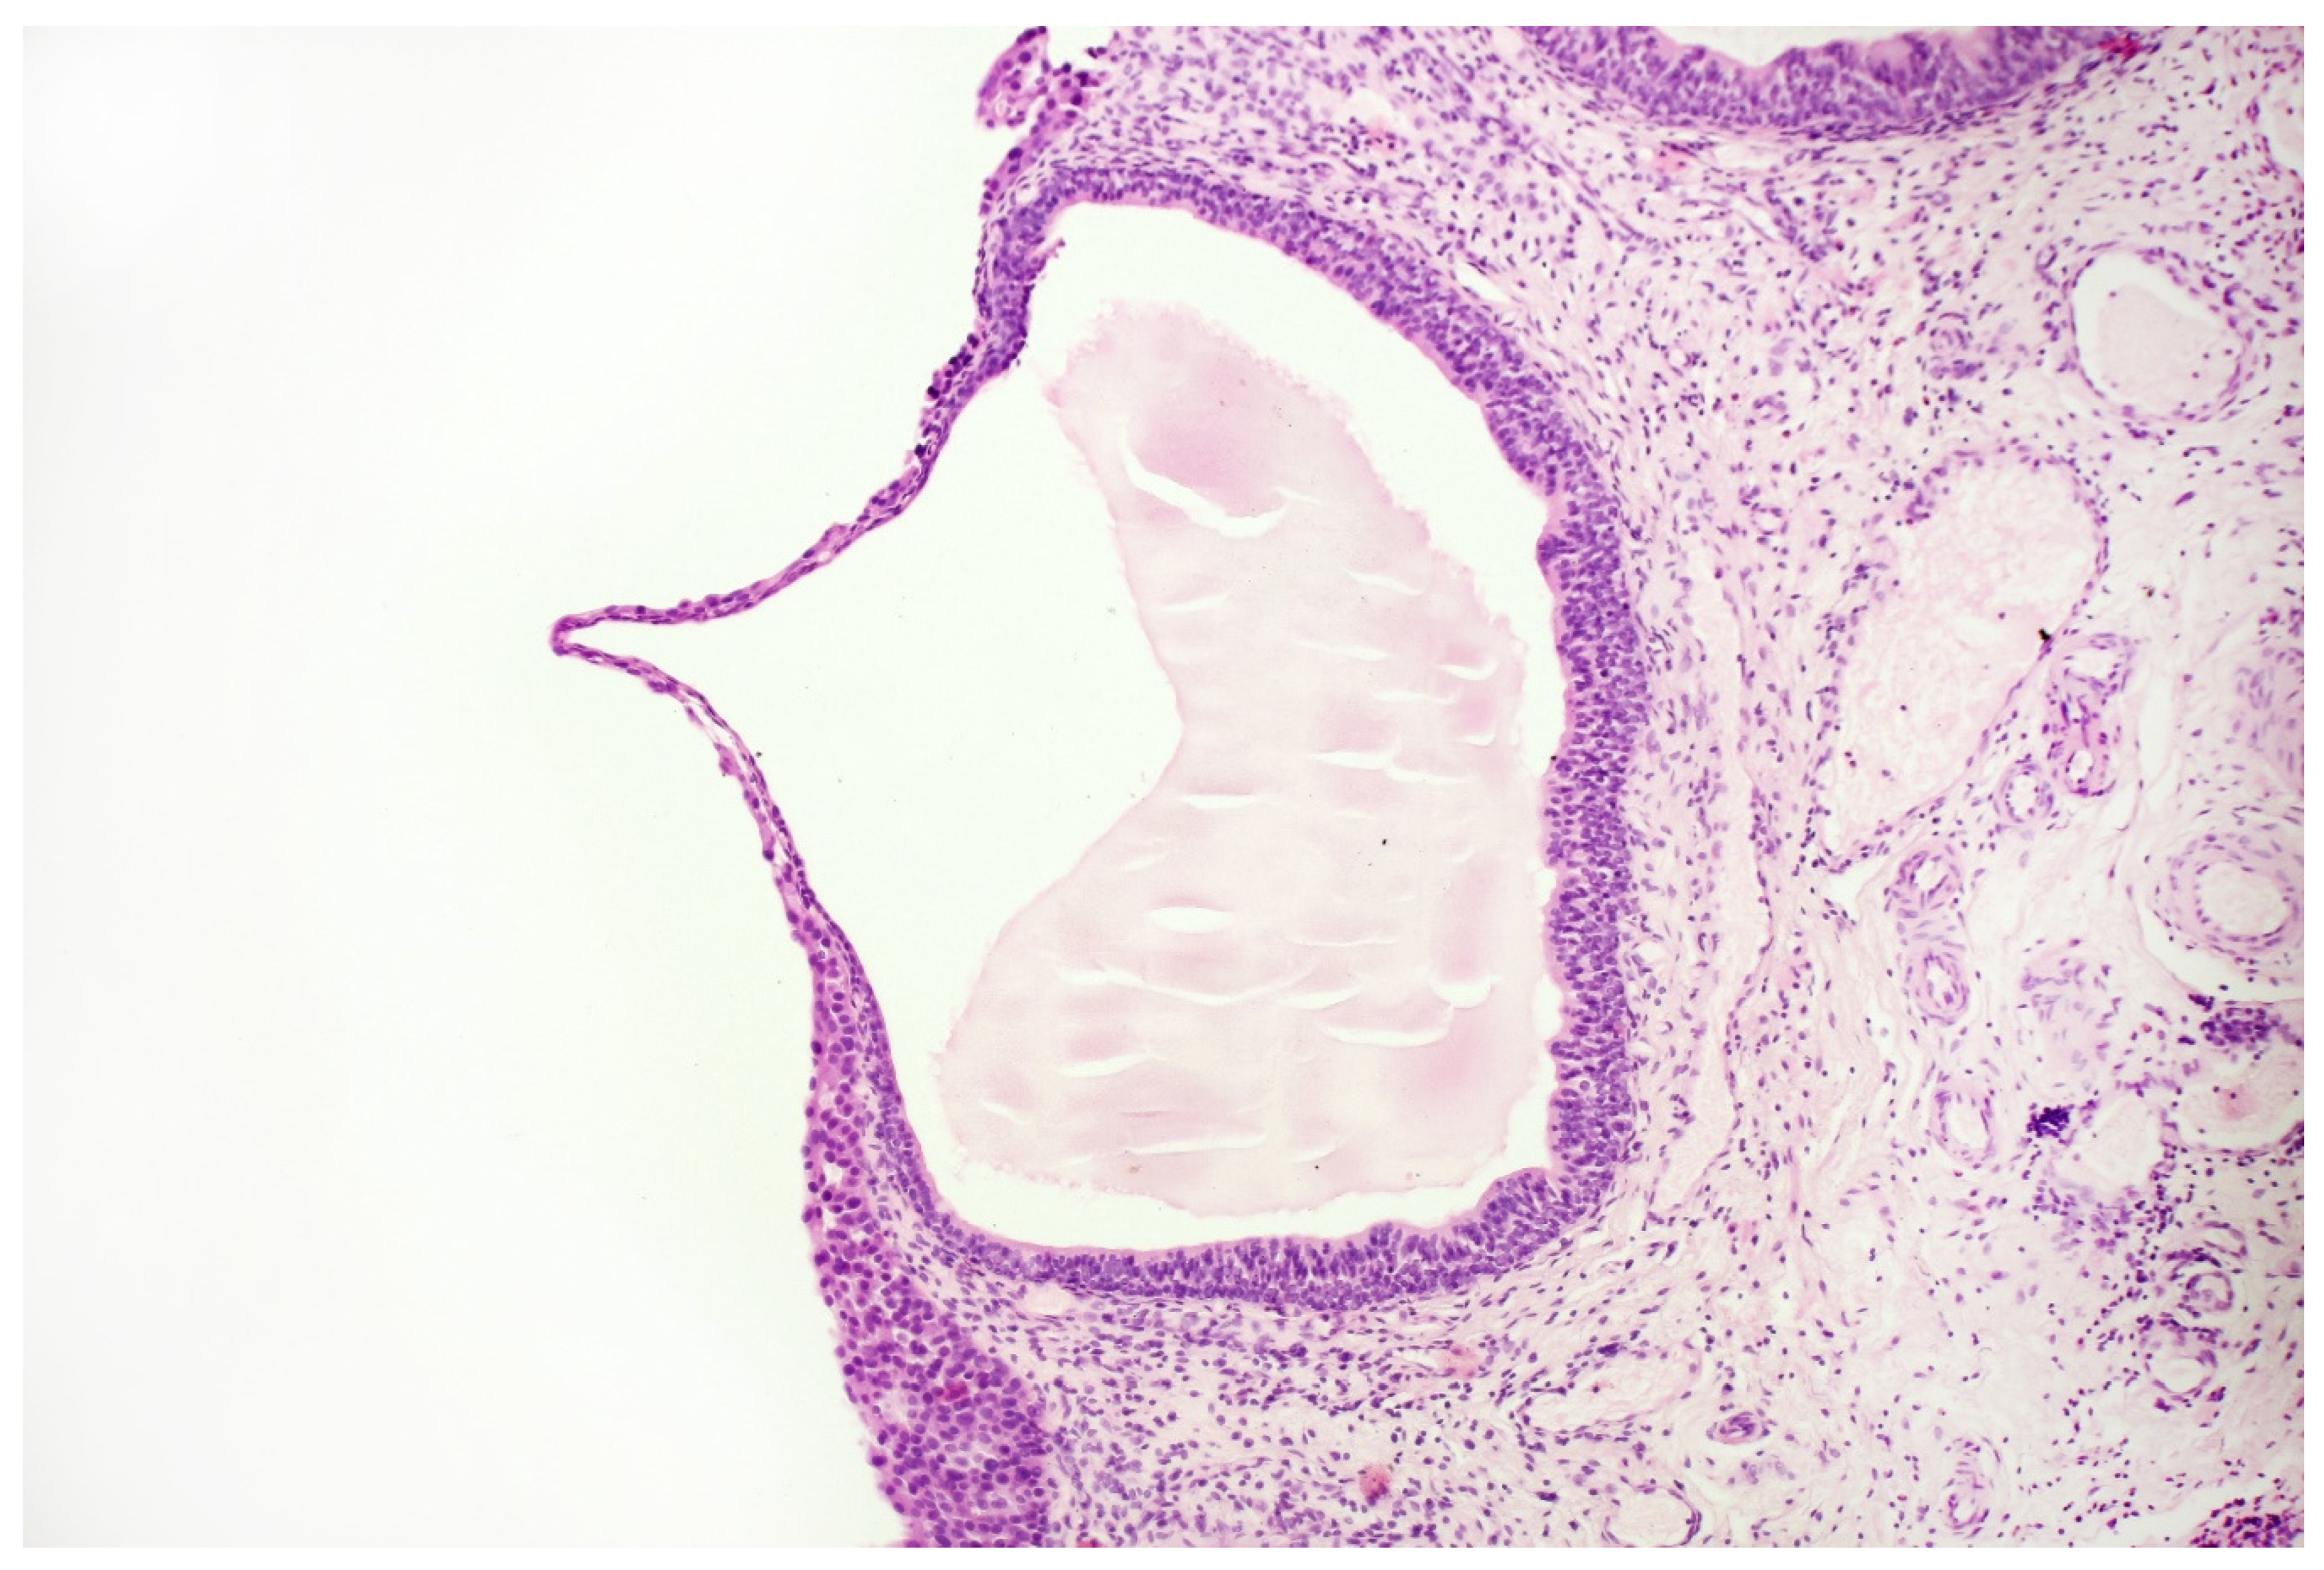

With the above-mentioned diagnostic data in hand, cystoscopy was carried out, undertaking a non-random bladder mucosa biopsy. Four specimens were collected, identifying urothelial carcinoma (HG CIS ICD-O code 8120/2) in each localisation and cystitis cystica, which could be responsible for the change seen in TRUS (see Figure 6 and Figure 7).

Figure 7.

Histopathological specimen—Haematoxylin and Eosin (H&E) staining. Cystitis cystica. The cysts are filled with homogeneous eosinophilic fluid and lined with the urothelial epithelium, the cells of which do not show signs of atypia. The atypia is visible in the epithelium, lying on the surface of the bladder in the immediate vicinity of the described cystic structures, in the submucosa of the bladder. There is no crawling of the atypical epithelium into these cysts.